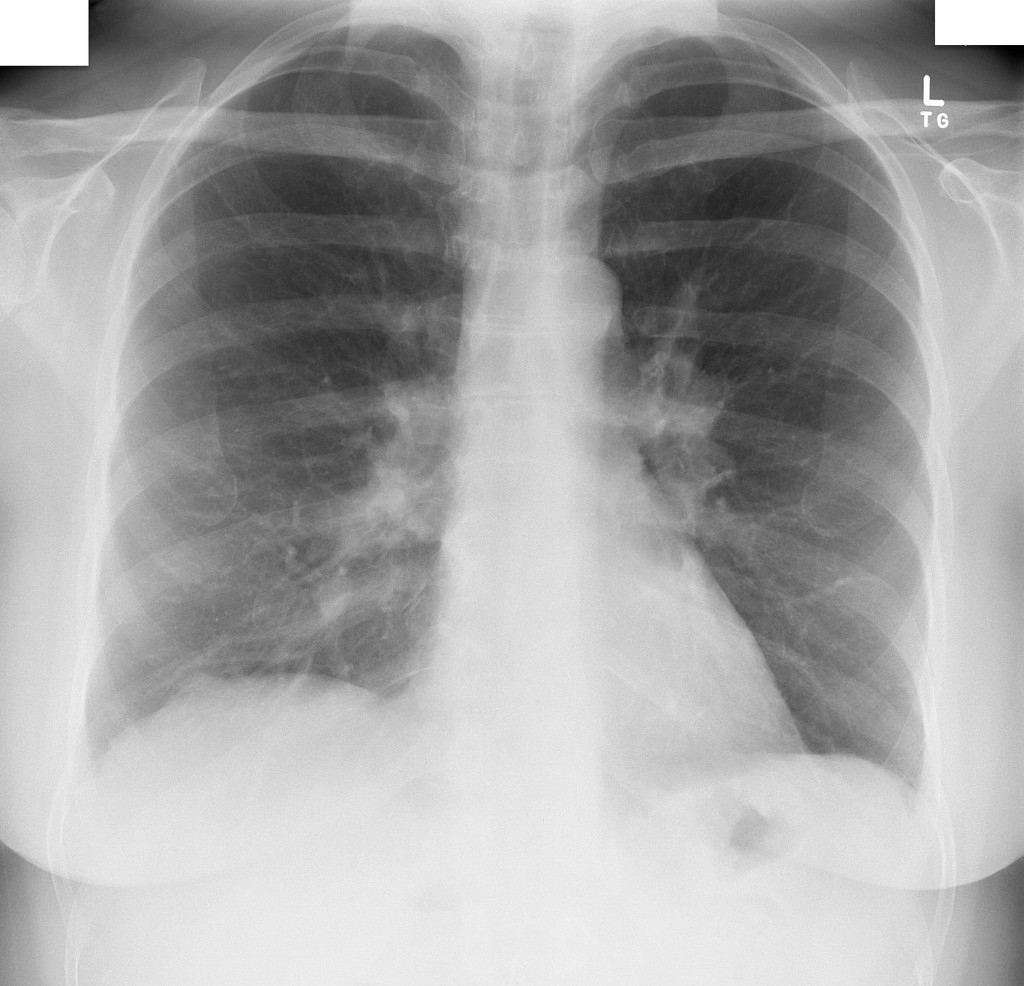

MULHER, 60 ANOS, REFERE “RESPIRAÇÃO CURTA” E TOSSE SECA HÁ VÁRIOS MESES

aumento e indefinição dos hilos pulmonares bilateralmente.

LINFADENOPATIA HILAR DEVIDO A SARCOIDOSE